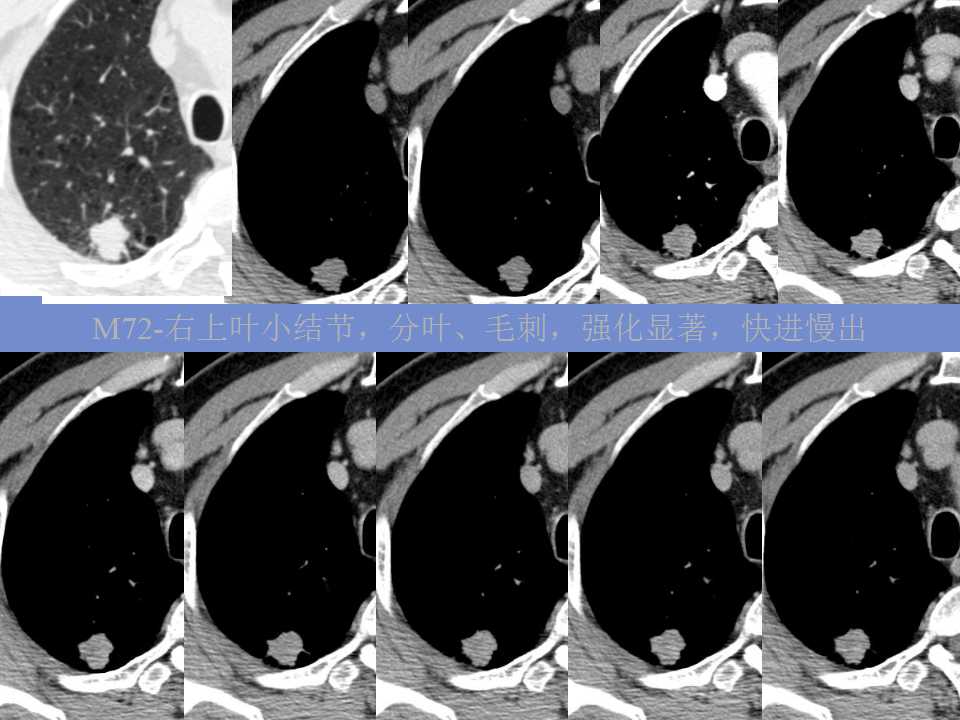

肺癌影像诊断